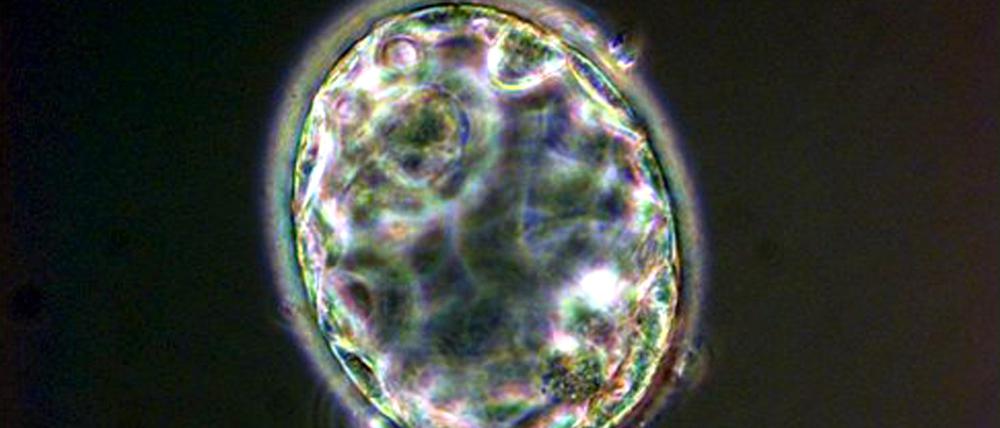

25 Jahre alte Klonentscheidung des Bundestages: Das Klonen verletzt die Menschenwürde nicht

Bleibt einem Paar keine andere Option als das Klonen, um zu einem genetisch verwandten Kind zu kommen, ist das vertretbar. Ein Gastbeitrag.

Am 21. März vor 25 Jahren hat der Deutsche Bundestag einstimmig den folgenden Beschluss gefasst: „Das Klonen von Menschen verstößt gegen die Würde des Menschen.“ Den Anlass gab die Geburt von Dolly, dem Klon-Schaf. Inzwischen hat sich die Aufregung gelegt. Die dystopischen Titelbilder mit den endlosen Reihen im Gleichschritt marschierender Kopien von Claudia Schiffer, Albert Einstein und Adolf Hitler sind verblasst.